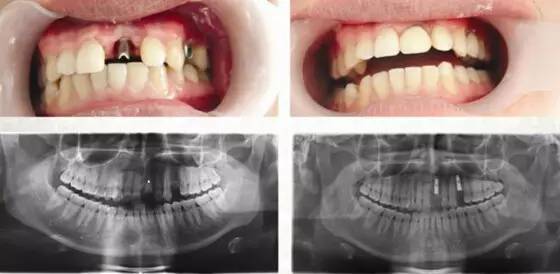

(经现场医生提供口腔CT图:种植很成功)

种好后,看着爸爸满口好牙,其女儿也很开心。